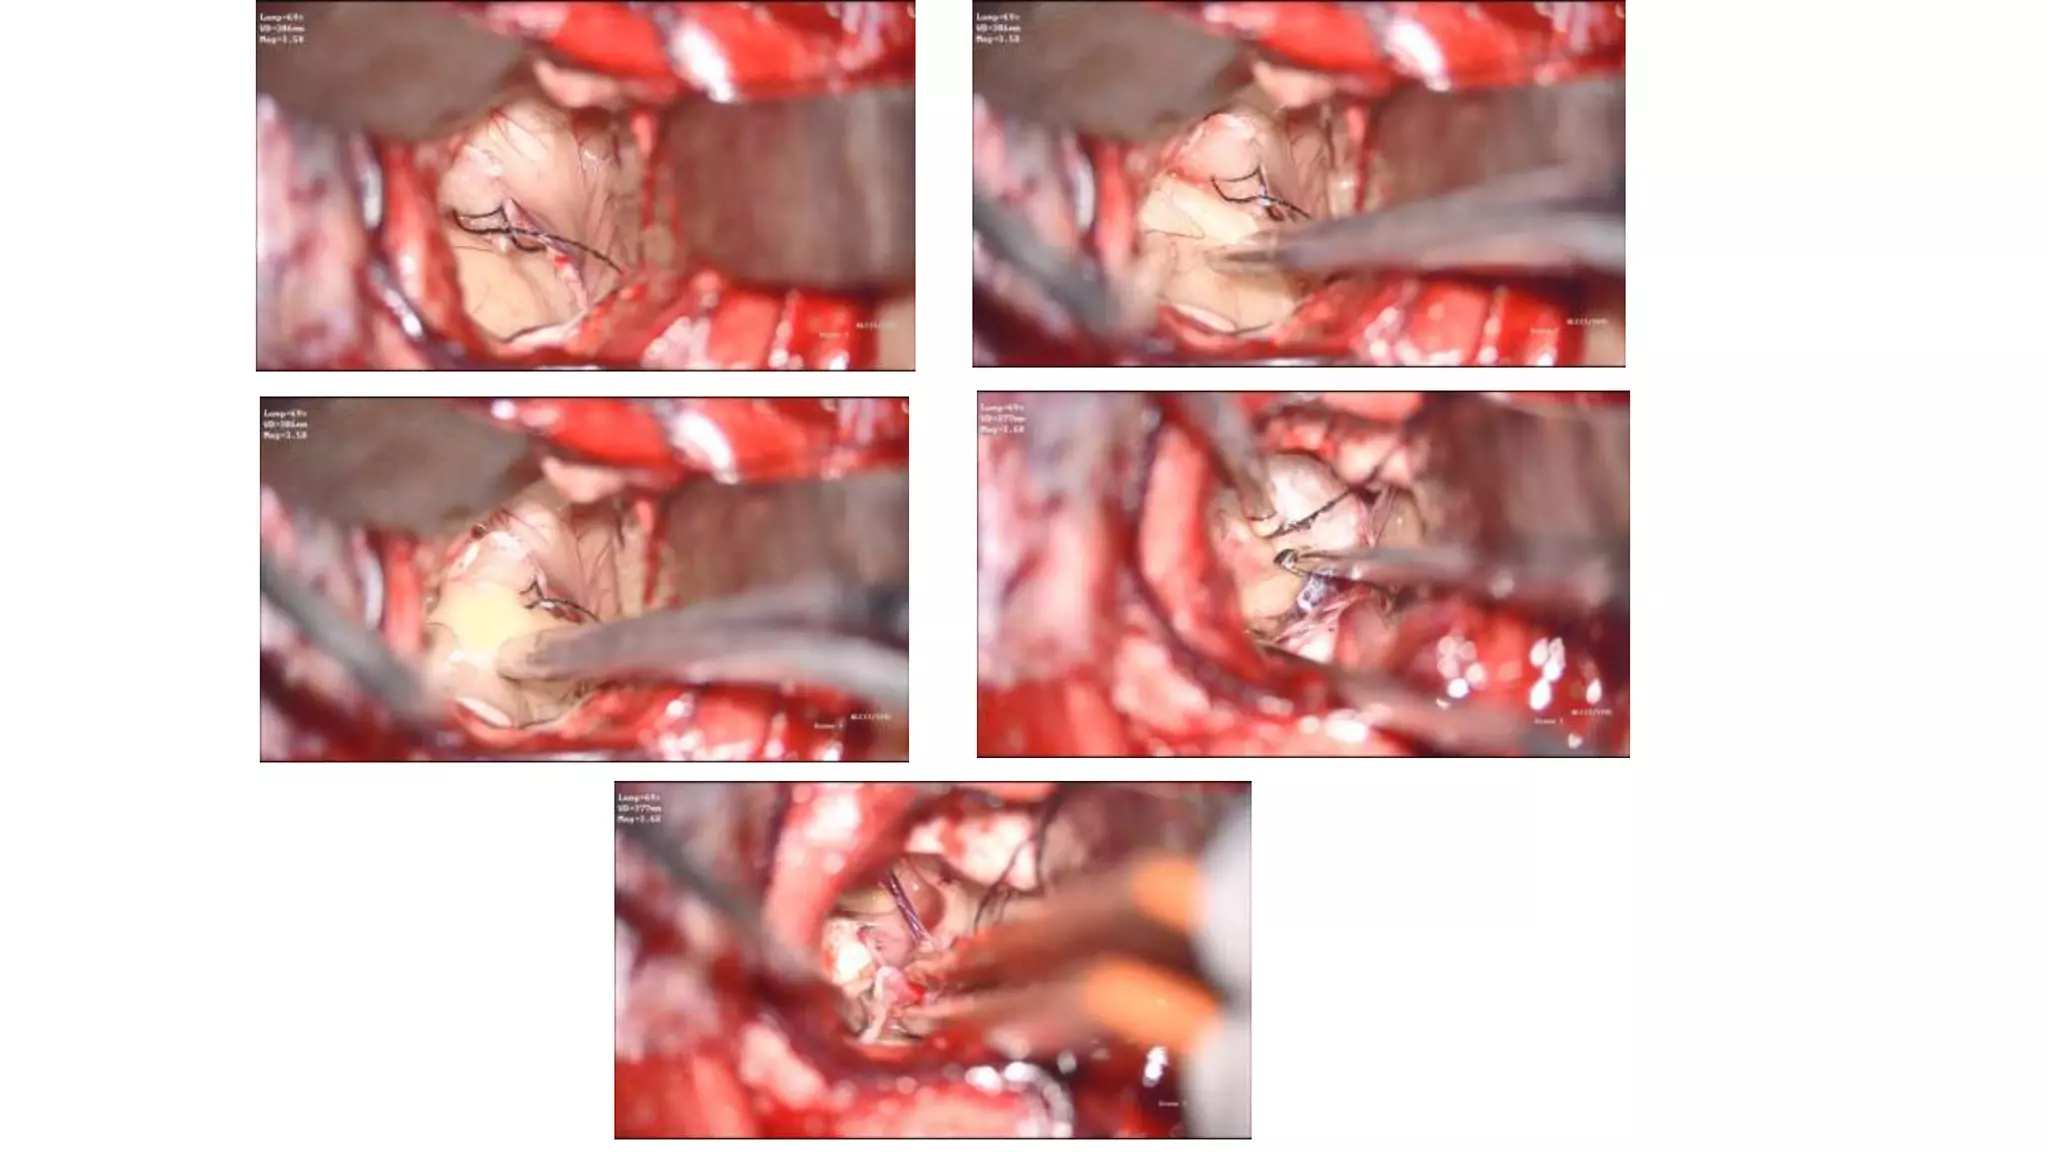

Transcortical approach:

• Entry point is through the middle frontal gyrus

• More lateral to medial approach of the ventricle

• Complete exposure of the lateral ventricles

• More dilated side is chosen or the non dominant side

• Preserving all bridging veins draining the frontal lobe prevents venous

infarction. Dissection of the terminal parts of these veins from the

dura or modified dural opening prevents their occlusion.